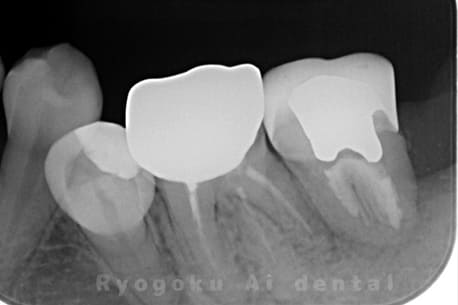

噛むと痛みが出る、とのことで来院した患者様です。他院での根管治療を終えてましたが、根尖病変を認めるため、マイクロエンドを行いました。

<リスク・副作用>

術後は痛み、腫れ、痺れなどの副作用が生じる場合があります。症状が再発する可能性があります。